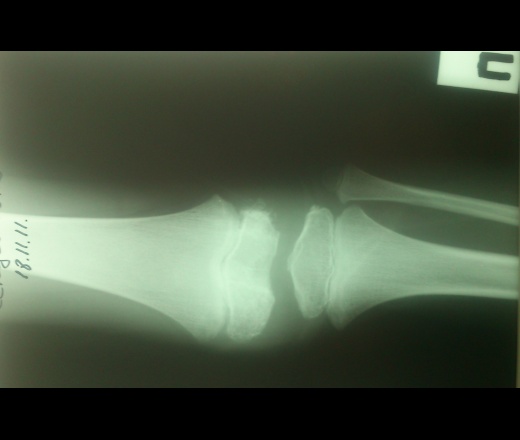

Мальчик 11 лет, жалобы на боли в коленных суставах в утреннее время. Движения в полном объеме, безболезненные, варусная деформация голеней с обеих сторон. У отца и деда выраженый гоноартроз.

Вопрос к детским рентгенологам (сама с детьми не работаю)-"лохматость" контуров суставных поверхностей бедренных костей у деток должна быть? А потом мне какие дополнительные тени кажутся, как суставные мыши у взрослых.

Патологии не вижу.

Костная структура соответствует возрастной норме. Единственное, что настораживает, великоват диастаз в межберцовом сочленинии. Я бы выполнила сравнительную рентгенографию обоих коленных суставов в прямой проекции с очень небольшой внутренней ротацией голеней 1 лучом на 1 пленке (с обязательным строгим соблюдением симметрии в укладке).

Костный возраст не соответствует 11 годам, по Садофьевой:

Полное окостенение эпифизов бедренной, большеберцовой и малоберцовой костей завершается несколько раньше (примерно в 8 лет)

Головки малоберцовок - как-то высоковато стоят по прямым снимкам, то ли укладка такая.

Вот-вот, и я об этом же. Дополнительные тени и нечеткость контуров.

Согласна, суставы не соответствуют возрасту, дополнительные тени - это добавочные ядра окостенения. Малоберцовые кости какие то длинные, щели межберцовых суставов широкие (в норме малоберцовая кость накладывается на большеберцовую). Вообщем, какие то диспластичные суставы. Костно-травматических изменений нет.

Мне периостальная реакция мерещится.

Согласен, но что-то ему болит. Скорее не рентгенологические проблемы, большая часть болей связана не с костной патологией.

Как правило, если имеют место "утренние боли", а если ещё и утренняя скованность, то нужно исключать различного рода артриты. Плюс ко всему нужно помнить о "болях роста". Варусная деформация с болями никак не связана, у детей вообще крайне редко любые деформации болят.

подозрение здесь на 2сторонний рассекающий остеохондрит ,ко-ый может иметь место в 30% случаев .слева в проекции дистального эпифиза бедра ,в проекции латерального мышелка бедра ,определяются точки окостенения ,один из находится на большом удалении от мышелка,чего не должно быть ,вероятнее всего яв-ся костным фрагментом.справа четко определятся костный фрагмент вогнутой формы (ядро окостенения всегда должно быть в этой зоне округлой формы ),с нечеткостью замыкательной пластинки (размытость).решить вопрос может мрт-будет отек и гипоинтенсивный сигнал во всех последовательностях(участок некроза)

Как детский ортопед, а совсем не рентгенолог, не могу без того, чтобы на самого ребенка не посмотреть. Прежде всего надо посмотреть на склеры, а уж если склеры голубые, то сразу к генетику вместе с папой и дедом. Если склеры не голубые, то и при этом есть вероятность несовершенного остеогенеза, формы которого весьма разнообразны, к тому же добавляются новые данные и клинические случаи, весьма разнящиеся.

Всё то, что Валентин Львович отметил стрелочками - не норма. Я бы описал на месте автора побробно снимок без заключения, а остальное предоставил ортопеду. У нас так и делается. И это правильно.